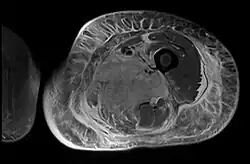

Axial fat suppressed T2 weighted MRI image showing hyperintense signal and enlargement of the left thigh adductor muscle group in diabetic myonecrosis.